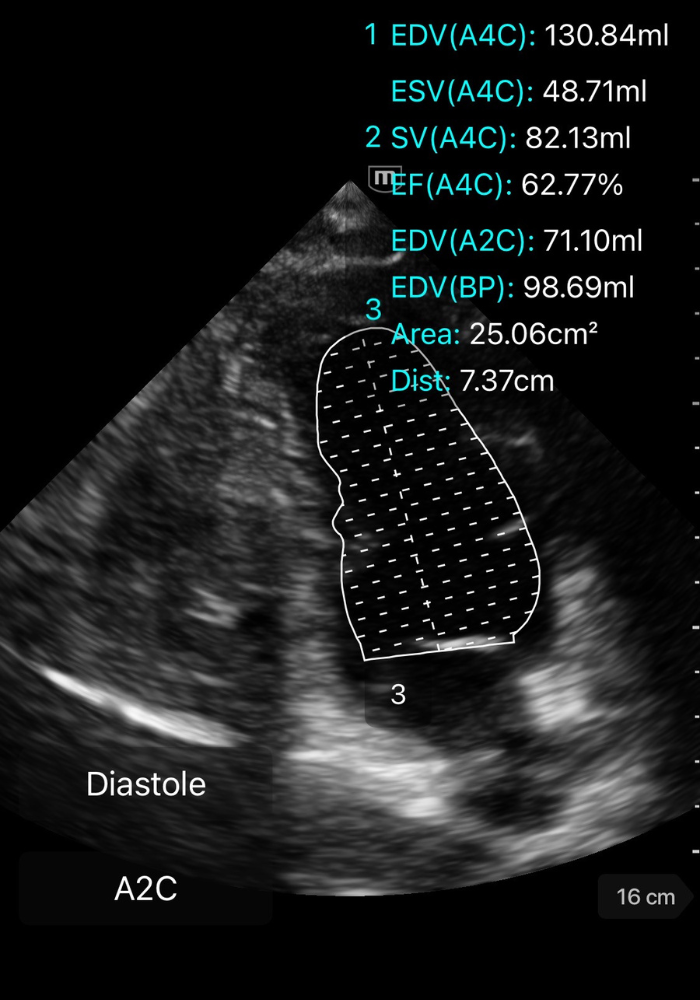

⚡️ Méthode de Simpson biplan

La méthode de Simpson biplan est la référence pour calculer la FEVG en échocardiographie transthoracique.

Elle segmente le VG en multiples coupes dont les volumes sont additionnés pour obtenir le volume télédiastolique (VTD) et le volume télésystolique (VTS).

🧭 Comment réaliser un Simpson biplan

1️⃣ Obtenir deux vues apicales orthogonales

- Apicale 4 cavités

- Apicale 2 cavités

Les deux doivent être strictement non tronqué.

2️⃣ Geler l’image en télédiastole et télésystole

-

Télédiastole = coupe où le VG est le plus large.

Télésystole = coupe où la cavité est la plus petite.

3️⃣ Tracer les contours endocardiques

Dans chaque vue (A4C puis A2C), en télédiastole et télésystole :

Placer les points de repère aux bases des feuillets mitraux.

Suivre précisément le bord endocardique jusqu’à l’apex.

Ne pas inclure les trabéculations ni les muscles papillaires dans la cavité.

➡️ La machine reconstruit ensuite un volume par empilement de coupes.

GIF ci-dessous: tracé du ventricule en diastole/systole (monoplane, démonstratif).

![]()